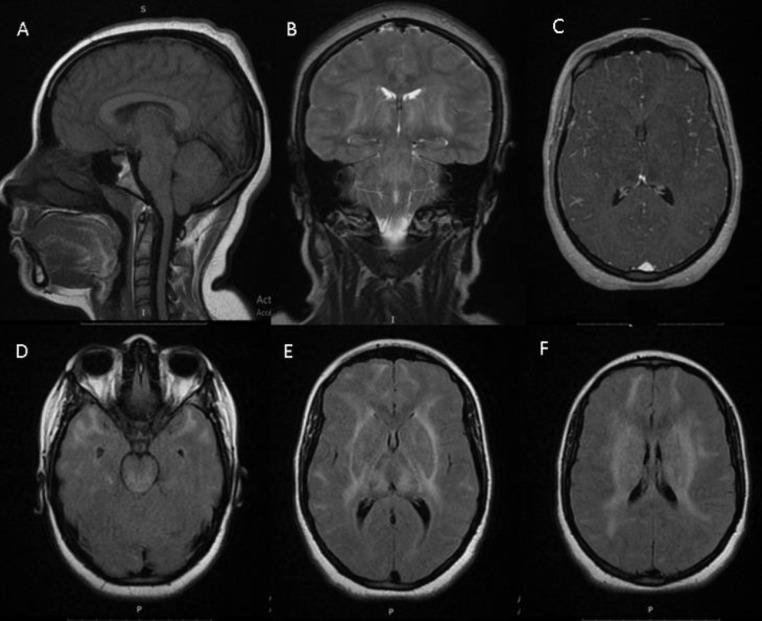

We described in this article a 19-year-old girl with an intracranial hypertension as an initial presentation of neuropsychiatric lupus. The brain MRI showed diffuse, bilateral and symmetrical white and grey matter hyperintensities. These lesions completely disappeared after 3 months of treatment. Diffuse cerebral edema with or without leukoencephalopathy in neuropsychiatric systemic lupus erythematosus is an extremely rare entity.

我们在本文中描述了一名19岁女孩,其以颅内高压作为神经精神性狼疮的初始表现。脑部磁共振成像显示弥漫性、双侧对称的白质和灰质高信号。经过3个月的治疗,这些病变完全消失。神经精神性系统性红斑狼疮中伴有或不伴有白质脑病的弥漫性脑水肿是一种极其罕见的情况。